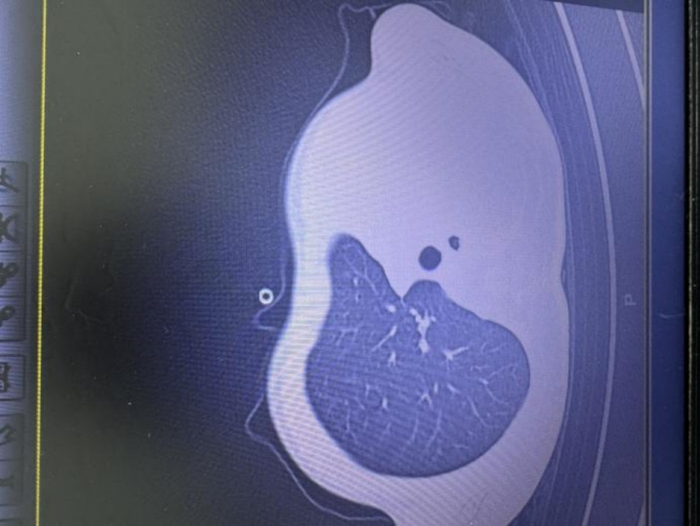

次日早上,小宇出现呼吸急促、嘴唇发紫、精神不振,家人急忙将他送往医院就诊,胸片检查发现左肺已变“白肺”,随时有窒息危险。

▲影像显示肺白了一半由于病情凶险,小宇被紧急送进PICU(儿科重症监护病房)。在气管镜下,医生发现小宇的气道里堵满了树枝状的“痰栓”,呼吸通道完全被塞住,气道内壁还有坏死组织。